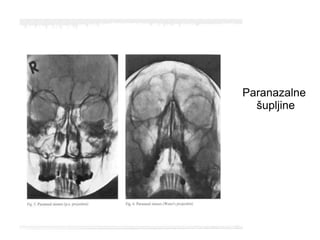

Paranazalni

sinusi

Paranazalne

šupljine